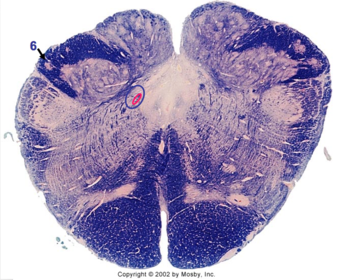

| Nucleus gracilis | |

| Nucleus cuneatus | |

| Fasciculus gracilis | |

| Fasciculus cuneatus | |

| Internal acruate fibers | |

| Lateral (external/accessory) cuneate nucleus | |

| Medullary pyramids | |

| Hypoglossal nucleus | |

| Hypoglossal nerve | |

| Dorsal motor nucleus of X | |

| Nucleus ambiguus | |

| Solitary tract | |

| Solitary nucleus | |

| ALS | |

| Medial lemniscus | |

| Medial longitudinal fasciculus | |

| Spinal tract of V | |

| Spinal nucleus of V | |

| Lateral (external, accessory) cuneate nucleus | |